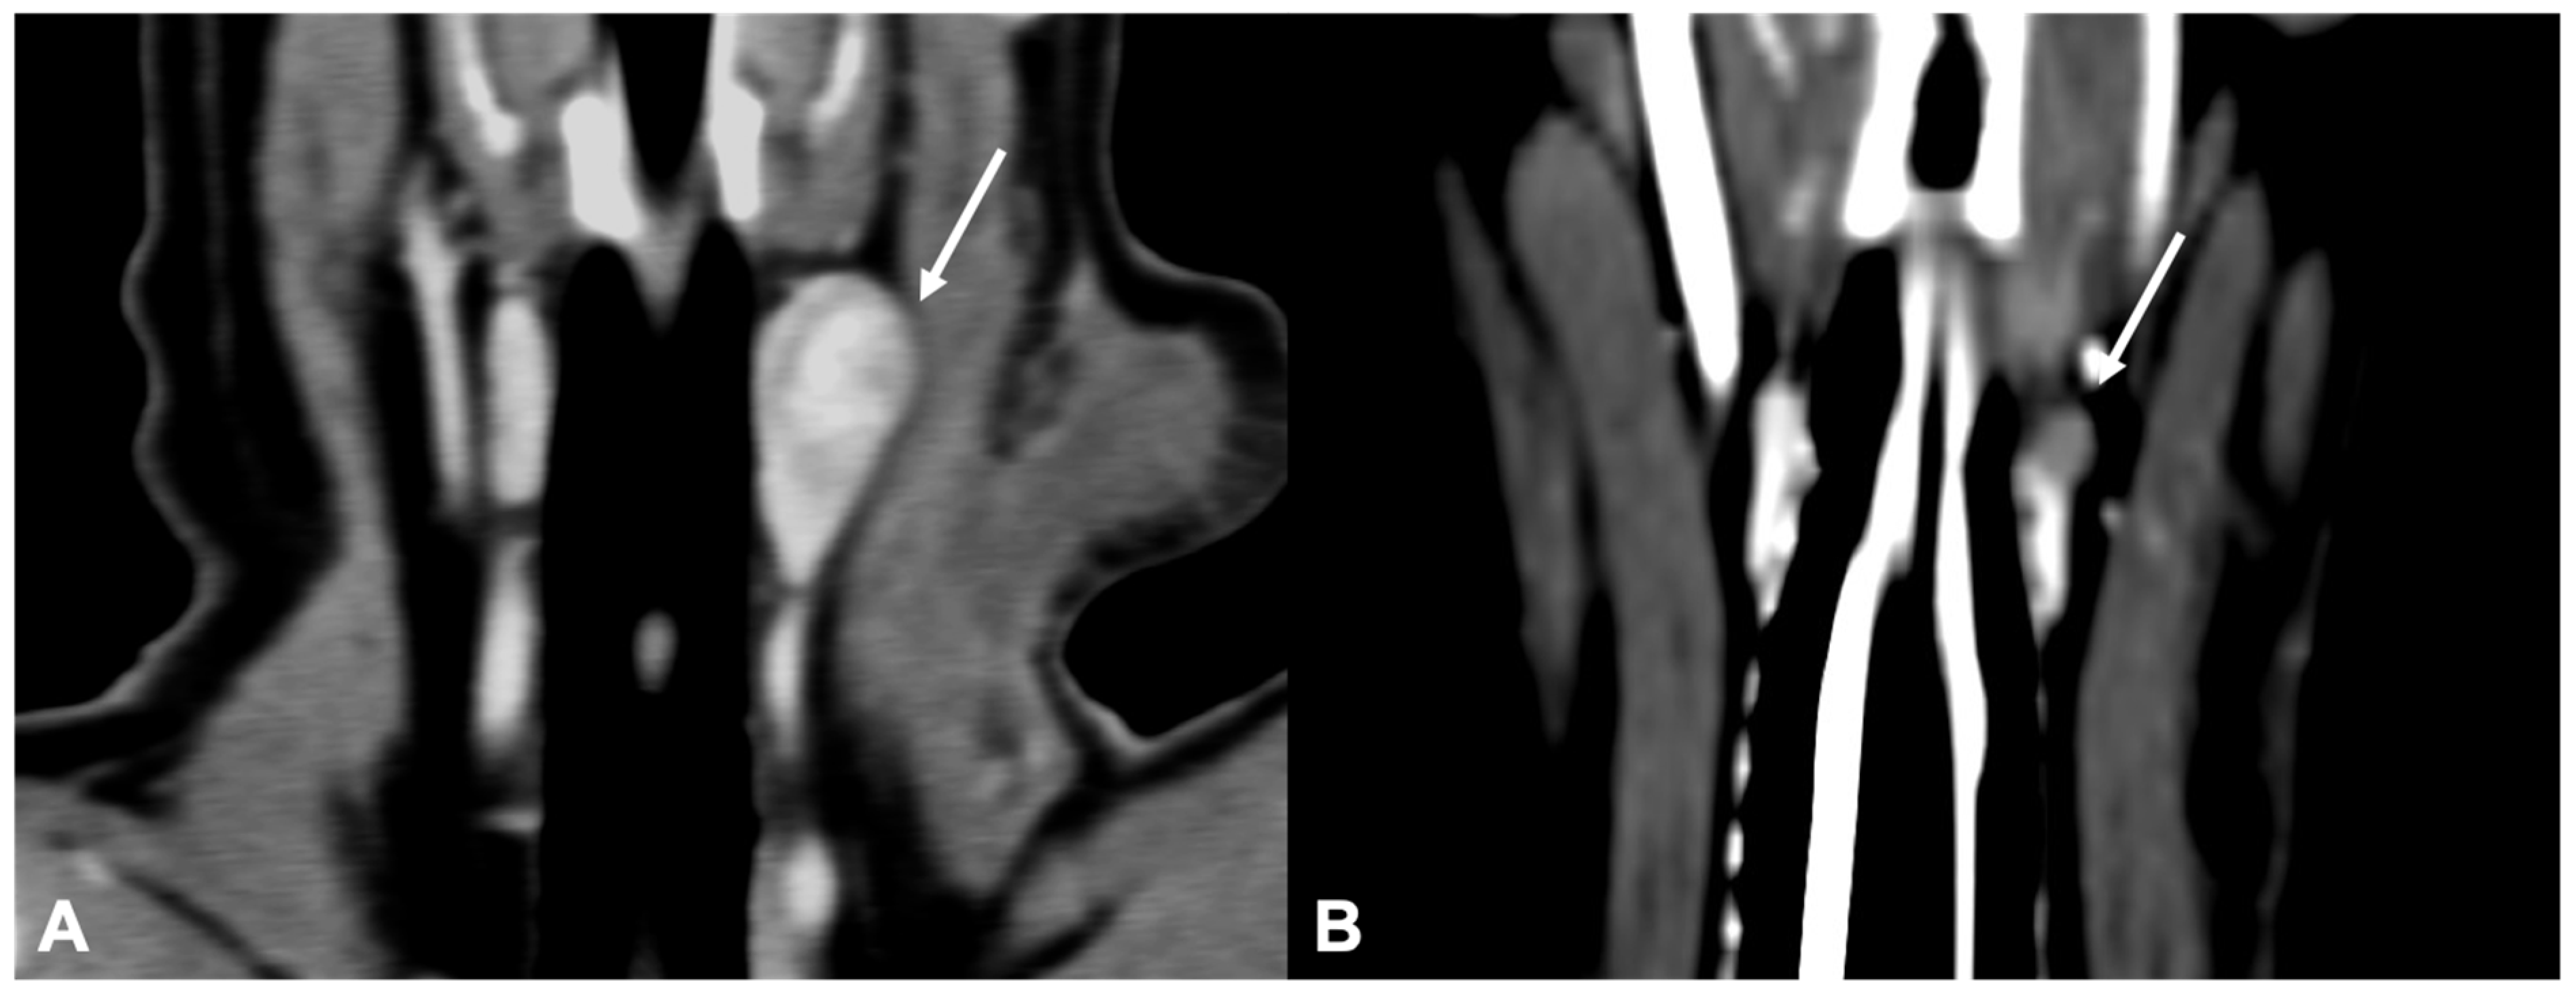

CT examinations were retrieved from the PACS (Picture Archiving Communication System—syngo.plaza, Siemens Healthineers, Milan, IT, USA) and analyzed using dedicated freestanding workstations and vendor-specific post-processing software (Syngo.Via, Siemens, Erlangen, Germany) by one author with 18 years of experience in multidetector-row CT imaging (G.B.). A combination of two-dimensional (2D) multiplanar reformations (MPRs) and three-dimensional (3D) volume rendered (VR) post-processing techniques were used (Figure 1). In particular, the dorsal reconstruction was routinely used in order to visualize both thyroid lobes and the parathyroid glands in the same image (Figure 2).

Figure 1.

Visualization of a normal right external parathyroid gland in a dog, post-contrast images. Two different 3D image volume techniques were used: multiplanar reformation (MPR), in which the three orthogonal imaging planes are seen (A) transverse plane; (B) dorsal plane; and (C) sagittal plane, and volume rendering (VR) technique (parasagittal view) (D).